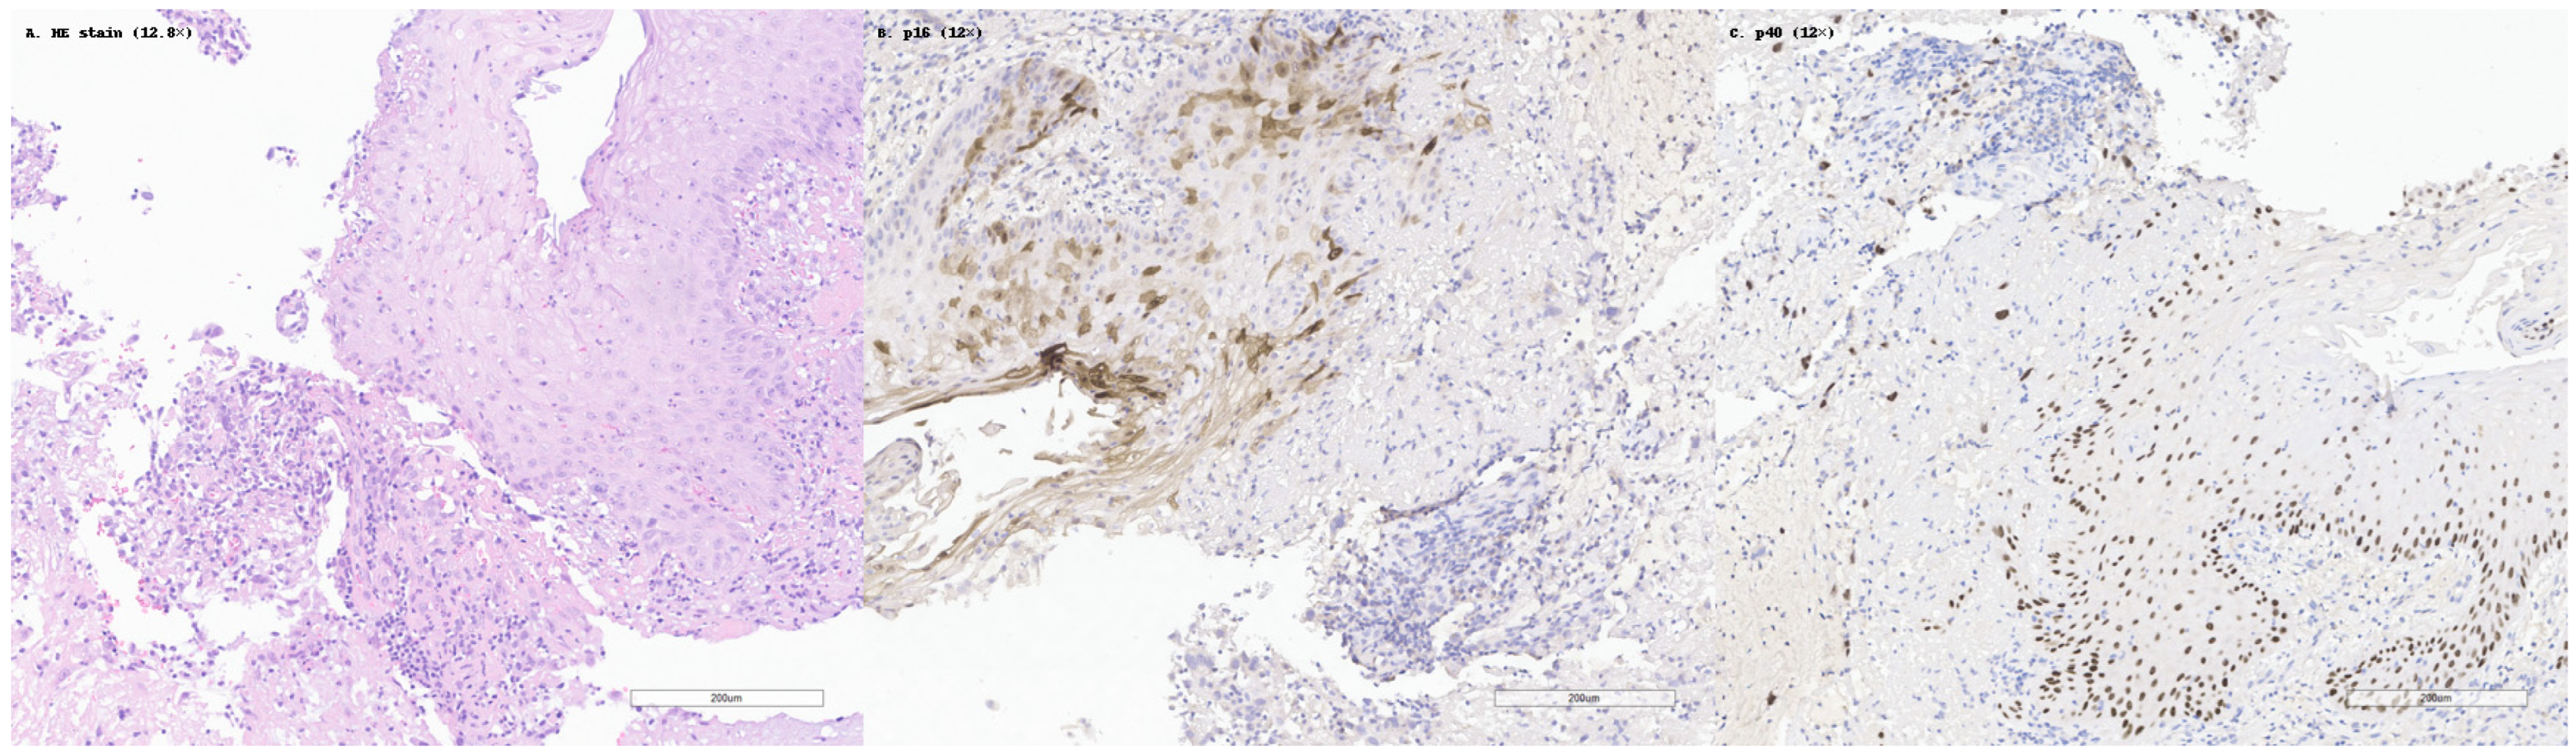

Among the studies analyzed, several immunohistochemical markers emerged as consistently useful in confirming squamous differentiation in SCC. The most frequently reported and validated markers were p40, p63, CK5/6, and desmoglein-3 (DSG3). These have become standard components in diagnostic panels, especially in cases with ambiguous morphology or limited squamous features. This is illustrated in Figure 2, which shows a case of moderately differentiated SCC with classic histologic features, diffuse p40 nuclear staining, and negative p16 expression.

Figure 2. Histopathological and immunohistochemical features of a moderately differentiated squamous cell carcinoma (SCC). (A) Hematoxylin and eosin (HE) staining reveals isolated tumor cells and cords of atypical squamous epithelial cells, moderate nuclear pleomorphism, and focal keratinization. (B) p16 immunostaining shows complete absence of nuclear and cytoplasmic reactivity in tumor cells, indicating lack of HPV-driven oncogenic involvement. Internal control in some of the intact squamous cell, adjacent to infiltrative component. (C) p40 demonstrates strong and diffuse nuclear positivity throughout the dispersed tumor nests, confirming squamous cell lineage and differentiation. Internal control in squamous cells of the basal layers. All panels are shown at original magnifications ranging from 12× to 12.8×, as indicated.